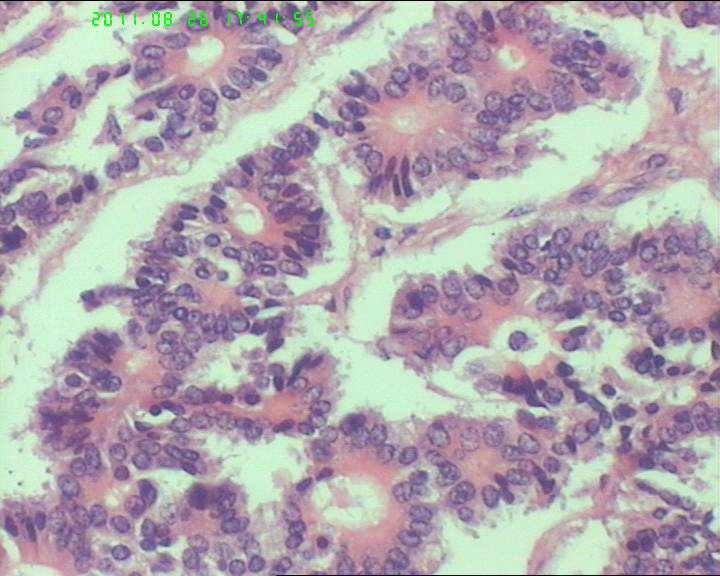

76岁女性卵巢巨大囊性肿物

卵巢肿物,大小18*14*10cm

本例瘤细胞虽排列呈菊形团或腺管样,但瘤细胞核内未见核沟,核的形态也不是典型的石榴子样,故颗粒细胞瘤是个排除性诊断,本例还有一个特点是瘤细胞团周围有一收缩裂隙,提示其最有可能是类癌,唯一不足的是未见丰富的血窦

此3张图片为宫颈处组织